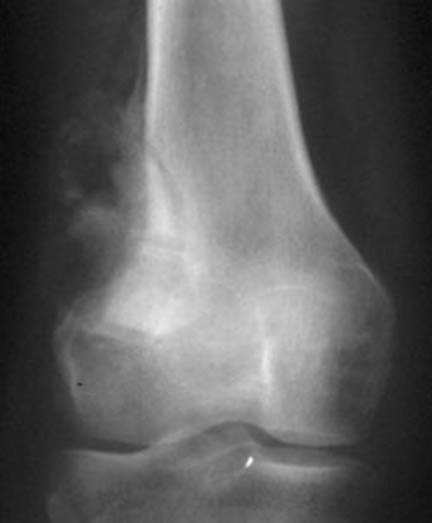

Radios

Jeune fille de 13 ans souffrant de son genou depuis 6 mois

Le signe le plus évocateur est la soufflure.